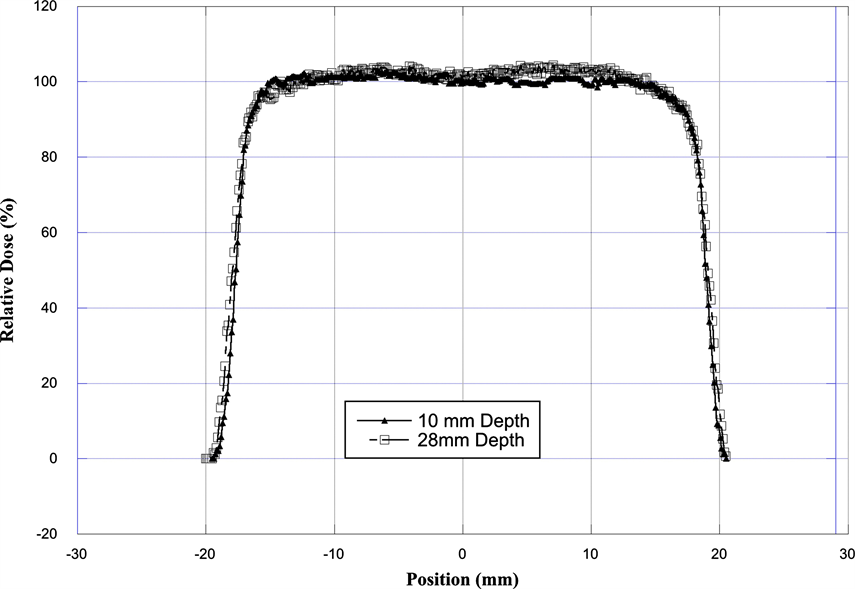

The flatness and symmetry of the radiation field at 10 and 28 mm depth were evaluated based on International Electro Technical Commission (IEC) specifications [23] [26] . The beam flatness specifications require that the maximum distance between the 90% dose and the edge of the geometrical field shall be <10. The symmetry of the beam, measured by the difference in dose at two points symmetrically placed to the central axis, was within 1.0% at both depths. The major factor in producing excellent proton beam flatness and symmetry on this facility is that we are not using any scattering material in the beam path to produce larger field.

Figure 3 shows an example of the beam profile at 10 and 28 mm depth. The relative dose measurement (i.e. penumbra between 90% to 20%) at 10 mm and 28 mm depth shows that lateral penumbra is sharper for profile at 10 mm depth as compared to profile at 28 mm depth. The analysis of the dose uniformity shows that the dose across the beam is within ±3% at a depth of 10 mm and within ±4% at a depth of 28 mm. Table 1 shows the characteristics of the radiation field.

Figure 3. Comparison of the transverse dose distribution of the radiation field as measured with EBT-3 Gefchromic film. The film was placed in a plastic phantom at a depth of 10 mm and at 28 mm.